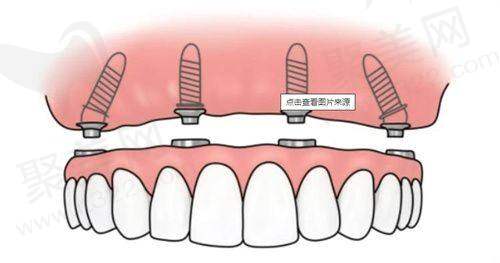

(六)瑞典诺贝尔 PMC

瑞典诺贝尔 PMC 单颗价格 13000 - 16000 元,是经典型号,使用寿命长,全口或半口种植患者可以优先选择。

(七)瑞典诺贝尔 Active

瑞典诺贝尔 Active 单颗价格 18000 - 22000 元,定位精细,适合复杂病例,有高难度种植需求的患者可以考虑它。